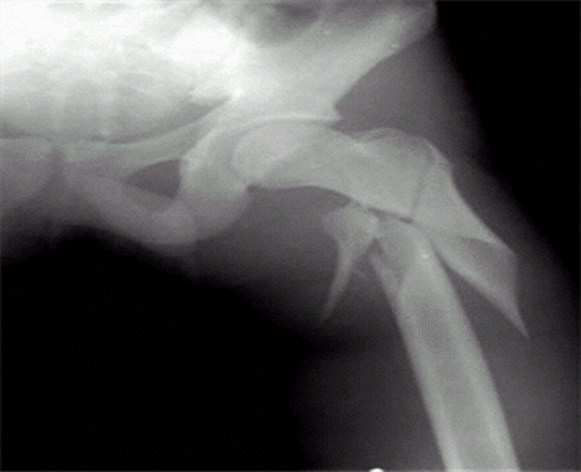

再來一題。第三題,看題。

ChatGPT似乎比較擅長骨科,那我們就再來一張骨折的圖,這個應該都能看出來是左側股骨幹骨折。

尷尬了,這,肩關節脱位?不得不説,還是有點像肩關節的。

突然,我意識到這樣不太公平,我們考試的時候還是有選項的,這不給人家選項直接讓人家作答,顯得我們人類有點刻薄。

於是,我加上了選項。

答對了。